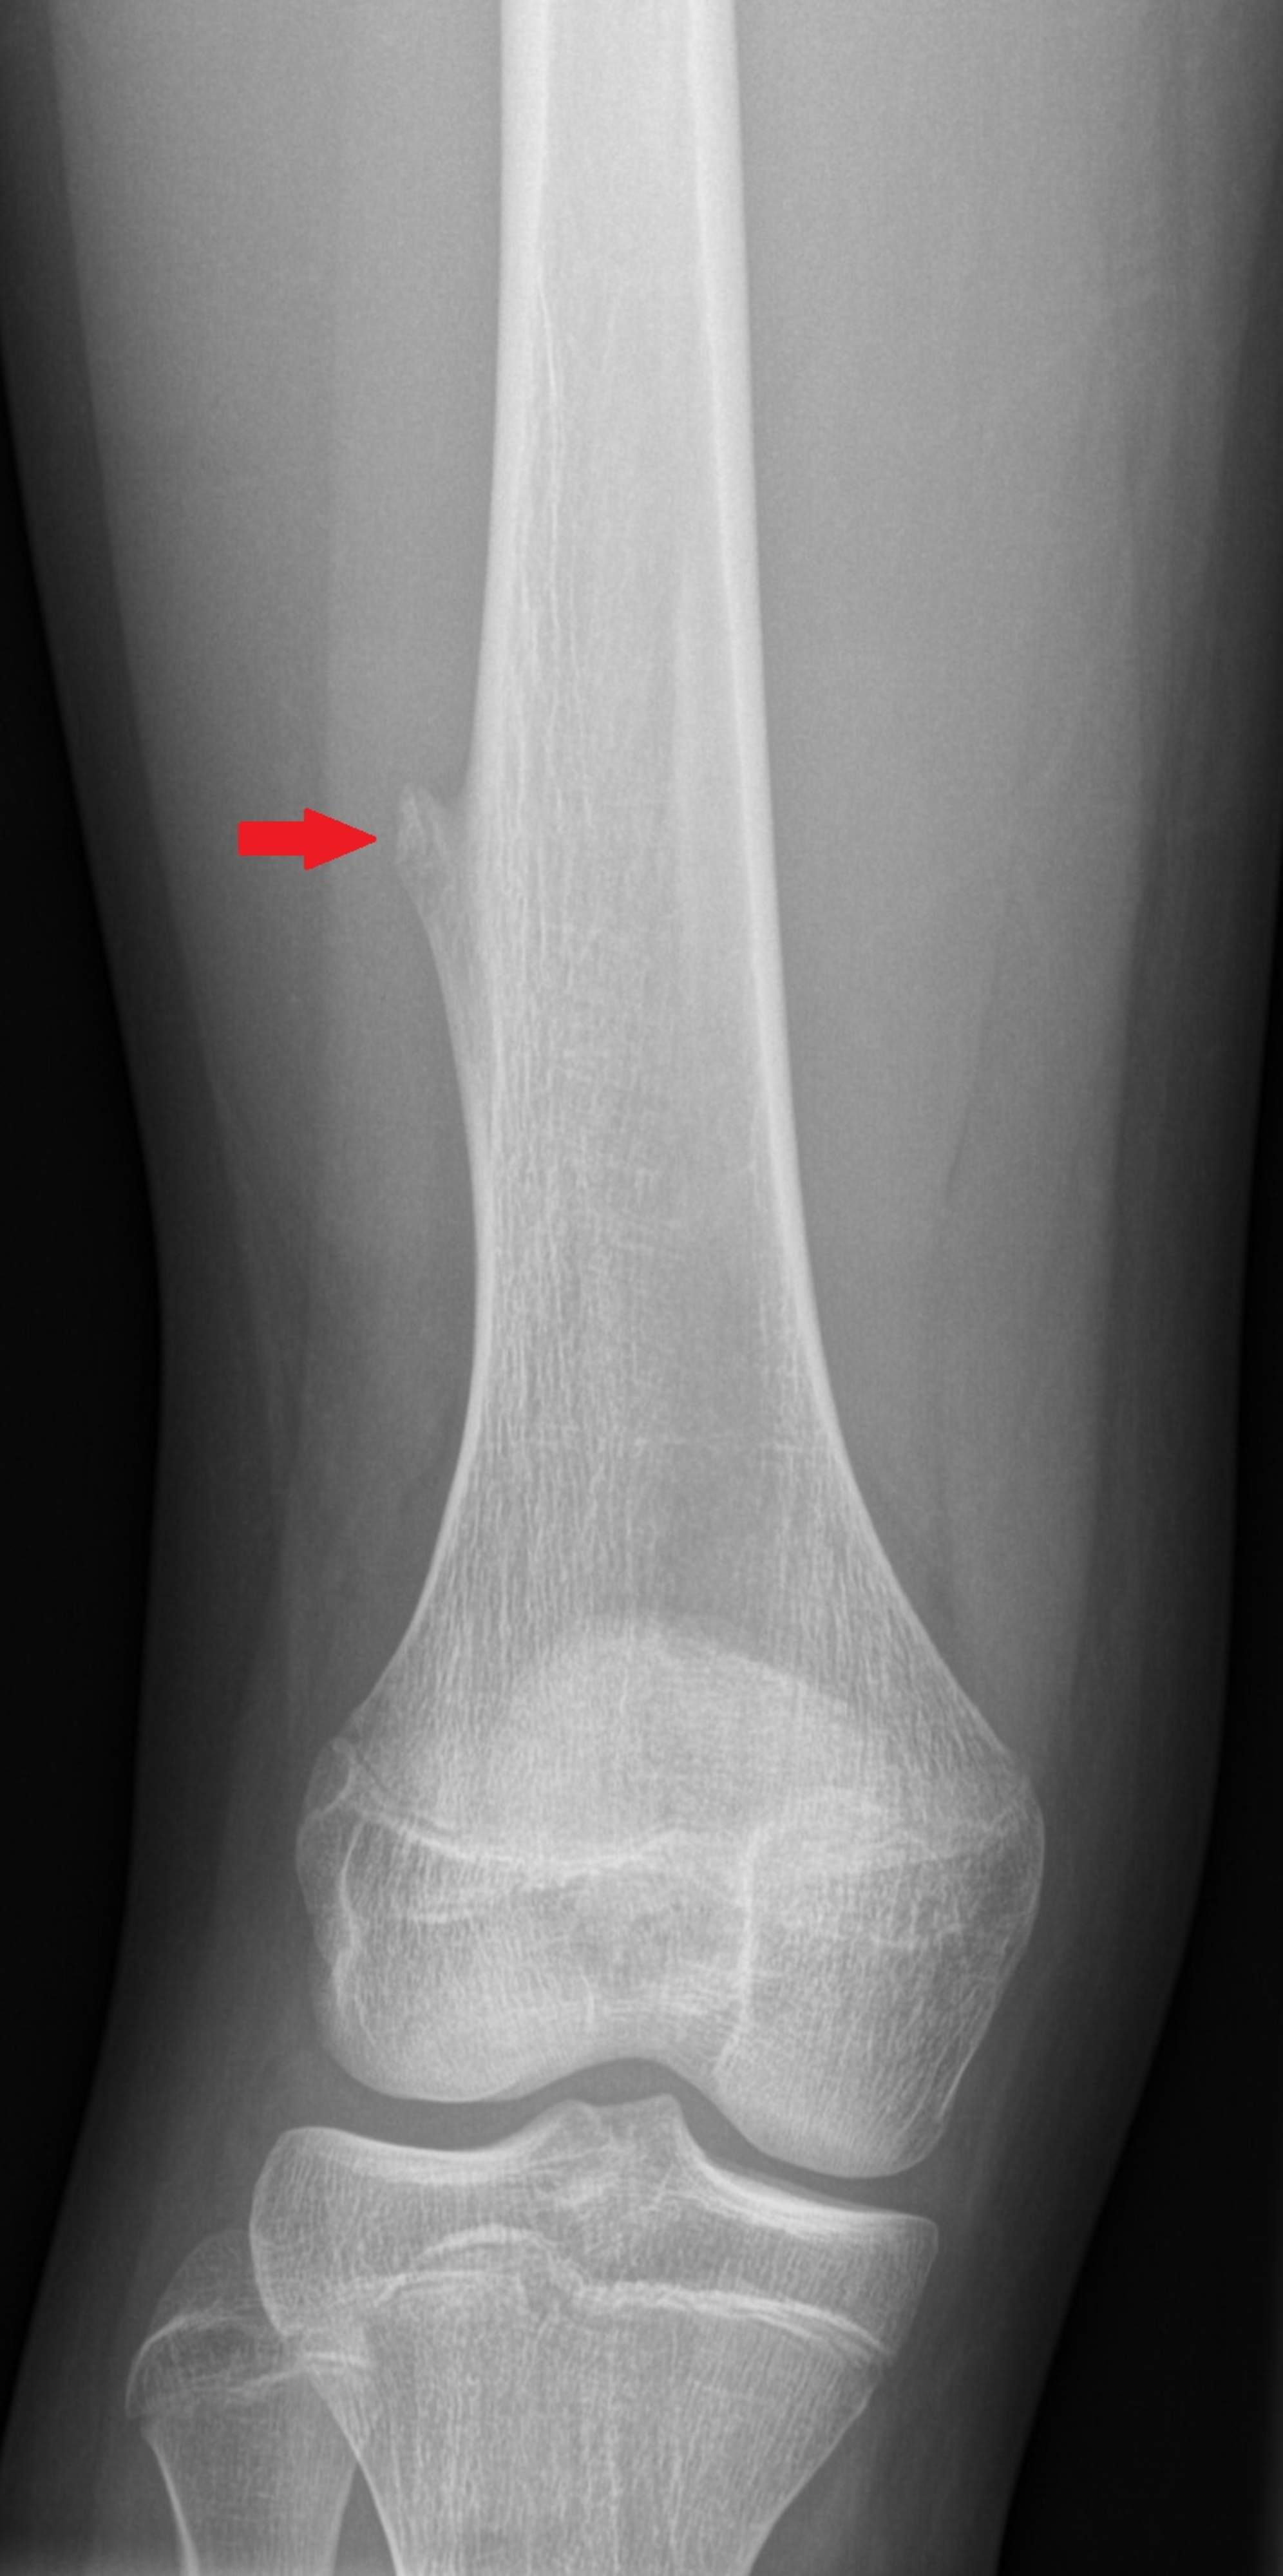

Syftet är att fastställa skelettumörens art och eventuella spridning. En undersökning utförd av en barnortopedisk kirurg är utgångspunkten för att fastställa behovet av fortsatta undersökningar. Röntgenundersökning är den primära metoden för att diagnostisera skelettumörer. Dessutom kan andra bilddiagnostiska metoder som magnetundersökning, datortomografi och isotopundersökningar användas på läkarens begäran för att avbilda benet och tumörens spridning från fall till fall. Syftet är att identifiera förändringar i benet så noggrant som möjligt så att behandlingen kan riktas in på rätt sätt. Ett vävnadsprov kan tas från förändringen och blodprov kan också tas från barnet. Dessa resultat utgör tillsammans diagnosen.